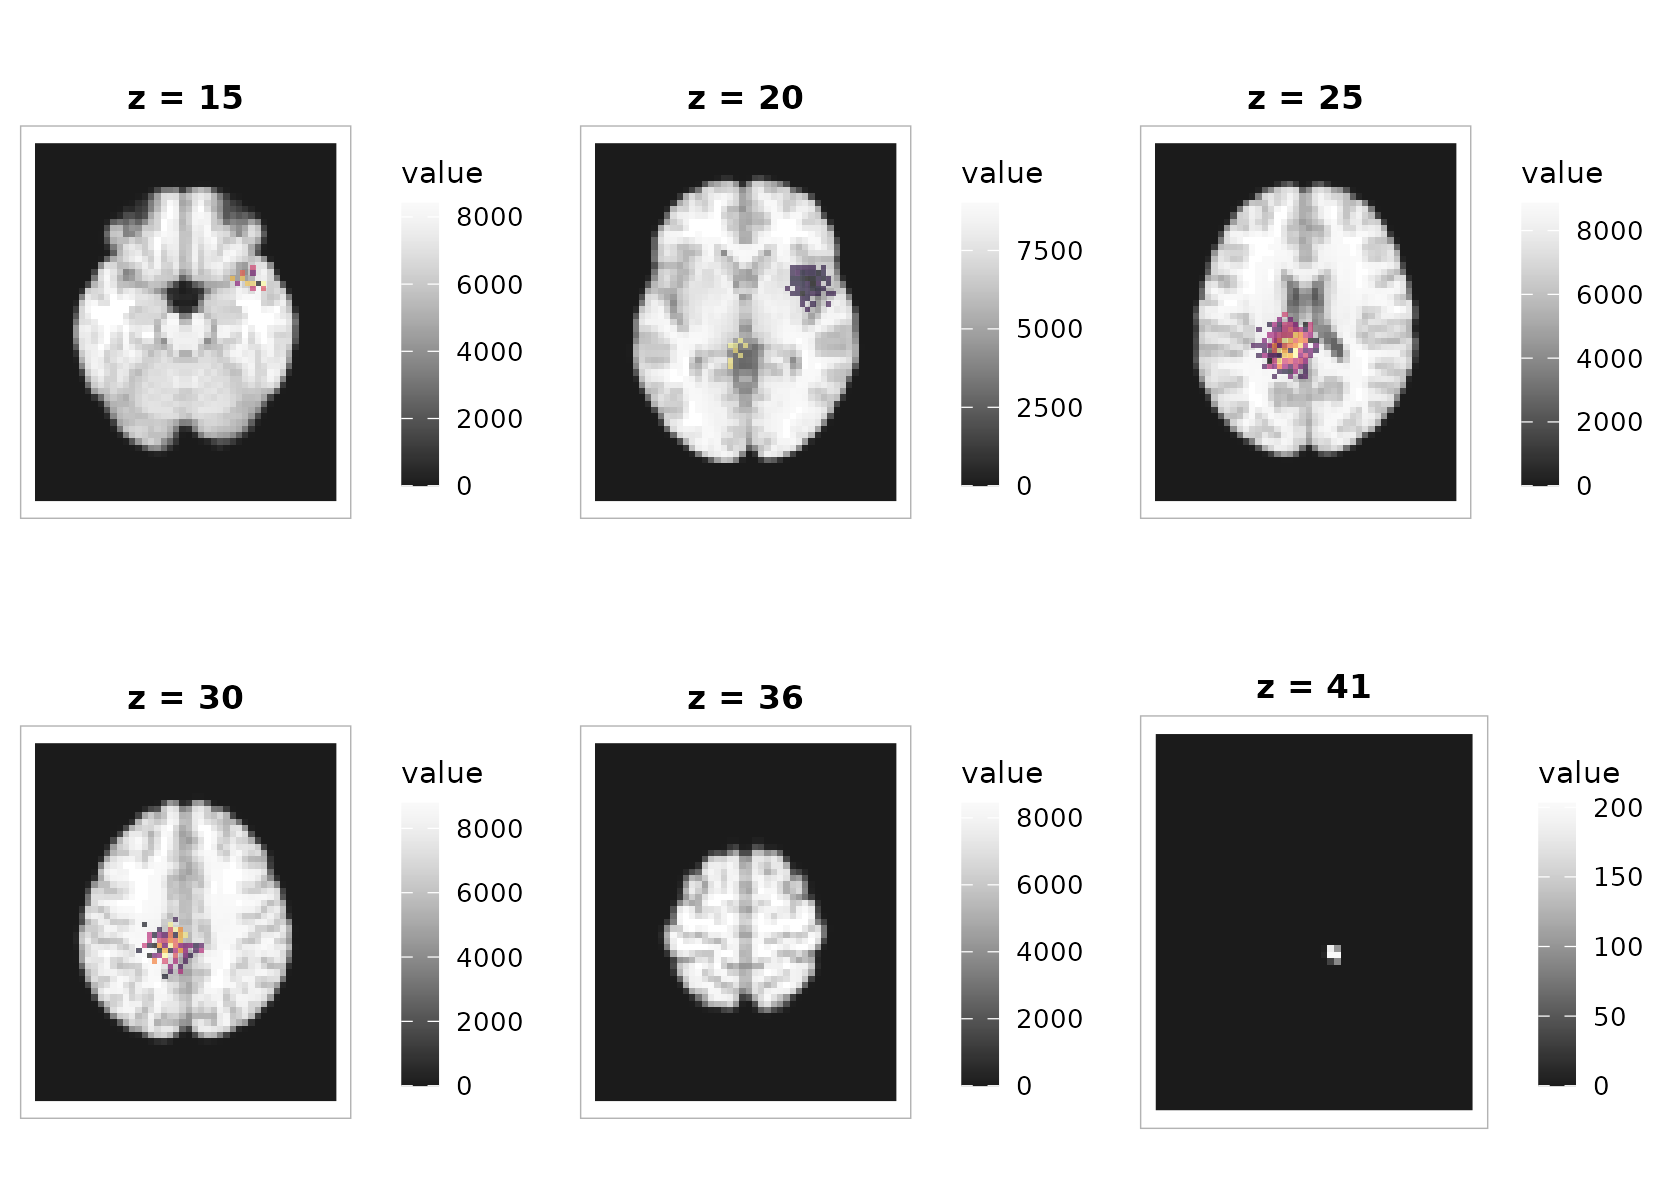

3) Overlaying an activation map on a structural background

The overlay compositor colorizes each layer independently (so each can use its own limits and palette) and stacks them as rasters. No extra packages required.

plot_overlay(

bgvol = t1, overlay = overlay,

zlevels = zlevels[seq(2, length(zlevels), by = 2)], # fewer panels for the vignette

bg_cmap = "grays", ov_cmap = "inferno",

bg_range = "robust", ov_range = "robust", probs = c(.02, .98),

ov_thresh = 2.5, # make weaker signal transparent

ov_alpha = 0.65,

ncol = 3, title = "Statistical overlay (threshold 2.5, alpha 0.65)"

)